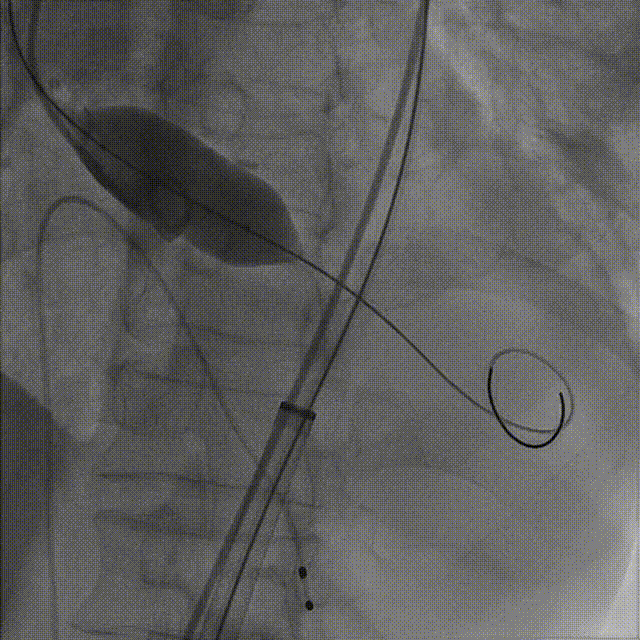

3.TaurusElite AV26号瓣膜定位及释放。瓣膜初始定位0位,开花后120次起搏,释放到工作位后造影显示瓣膜位置较深,形态敞口状,预估释放后存在进一步下滑风险,决定回收调整。

第一次瓣膜初始定位

第一次工作位造影

4.瓣膜第一次释放下滑明显,第二次初始定位瓣上2mm,缓慢释放开花,提拉输送器,快速释放到工作位,造影显示位置良好,少量瓣周漏,决定脱钩

第二次瓣膜初始定位及释放

第二次瓣膜脱钩